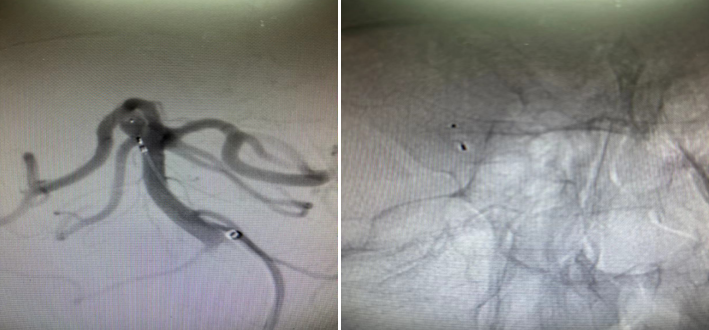

患者28岁,因反复头痛头晕在当地医院检查提示基底动脉顶端动脉瘤。患者患有高血压,基底动脉动脉瘤随时可能破裂致自发颅内出血,严重时可能致残致死。因该位置手术风险较大,地州医院无法手术,于是患者辗转来到樱花动漫 神经外科一病区。入院后,神经外科一病区为患者行全脑血管造影,提示右侧小脑上动脉动脉瘤。

该动脉瘤位于右侧小脑上动脉及大脑后动脉之间,宽颈,常规栓塞较为困难,支架置入难度较大,若置入支架辅助栓塞,后期患者需抗凝抗血小板治疗较长时间;开颅手术夹闭则创伤较大,恢复时间较长。蒲军主任在仔细阅读患者DSA造影资料后,提出可行现最新的自膨式瘤内栓塞系统治疗该动脉瘤,在告知家属病情及相关情况后,患者家属同意行该手术。

经过周密的术前检查,在蒲军主任的指导下,黄晓斌及张明副主任医师、王和平博士团队顺利为患者实施了自膨式栓塞系统小脑上动脉动脉瘤栓塞手术。手术时间20分钟,完整填塞动脉瘤,术后造影提示动脉瘤未显影,周围各支重要血管血流正常。术后,患者恢复良好,无任何神经功能障碍,无需服用任何特殊药物,并于3天后出院。